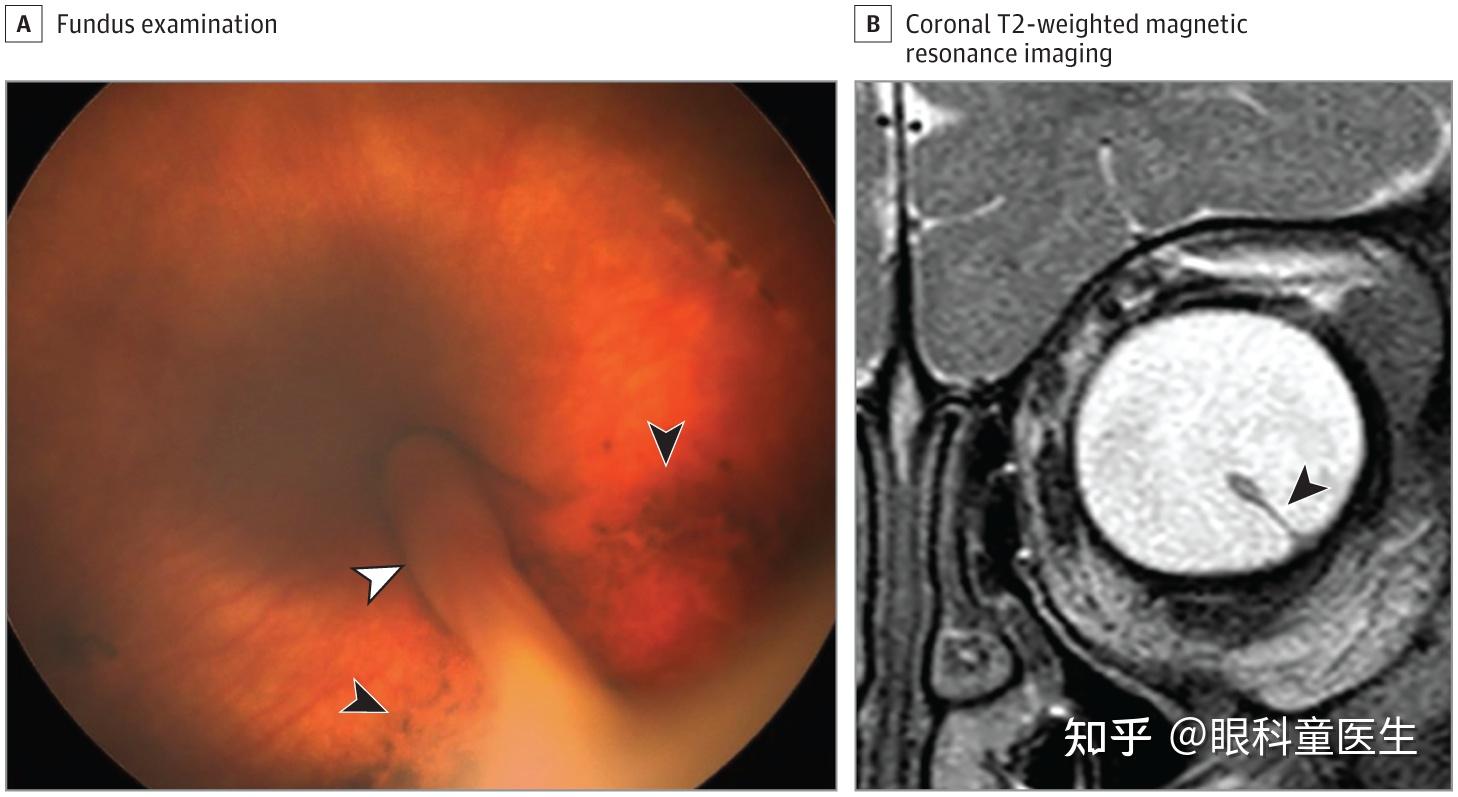

先天性视网膜异常4先天性视网膜皱襞